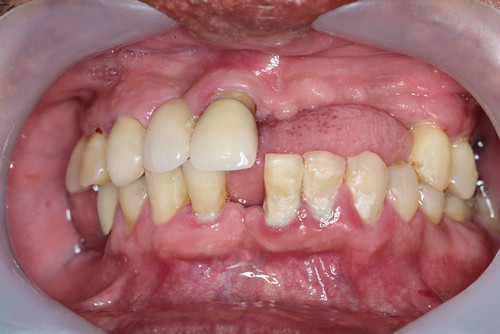

Хронические формы заболевания протекают более агрессивно. Это касается и обострений патологического процесса. Особенность патологии в том, что она часто поражает ткани и вызывает из изменения. Нередко образуются гранулемы и крупные кисты. Лечение хронического периодонтита обычно оперативное, хирургическое. Когда зуб еще можно сохранить, проводится резекция верхушки корня или полное удаление корня. Однако это не гарантия клинического результата. Часто зуб сохранить невозможно. Тогда проводится удаление. После коррекции состояния лунки, устранения воспалительного процесса решают вопрос имплантации или иного протезирования.